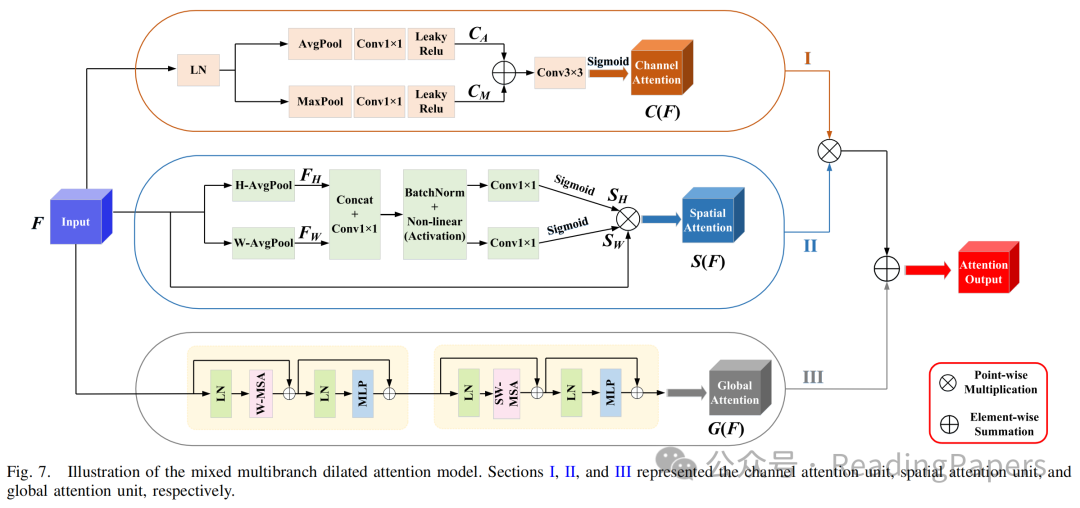

神经网络中浅层和深层特征具有不同的表示能力。因此,迫切需要寻求一种解决方案,以有效弥合编码和解码阶段相应特征之间的语义差距,同时最小化由采样过程引发的信息丢失。为此,作者引入了一种混合多分支扩张注意力(MMDA)模型,从三个维度(即通道、空间和全局上下文)映射特征,综合优化提取特征的信息丢失。该方法有效地减少了提取特征中的信息丢失,从而帮助解码器准确恢复特征图的原始分辨率。作者将MSAF每一层(除了最深层的下采样层)提取的特征图与相应的CNN特征金字塔输出融合。然后,通过跳跃连接将该组合输入到MMDA模块中进行特征提取。最终,该方法实现了与相应解码器层的和谐特征融合。MMDA模型由三个单元组成,包括全局自注意力单元、通道注意力单元和空间注意力单元,如图7所示。

通道注意力单元(图7的第I部分)主要获取图像纹理信息,同时关注每个通道的特征交互。对于给定的输入特征图,通过MaxPooling和AvgPooling操作沿空间轴提取特征信息。获得的特征图和分别经过1×1卷积和LeakyReLU激活,然后进行逐元素加法操作。最后,使用Sigmoid函数获得通道注意力图。具体流程如下:

其中,表示通道注意力图,表示逐像素求和。

空间注意力单元(图7的第II部分)的主要目标是识别网络中最重要区域以进行进一步处理。受先前使用坐标注意力(CA)模块的工作启发,作者采用CA技术作为MMDA模型的空间注意力部分,以编码具有精确空间位置信息的特征表示。该方法分为两个子步骤:坐标信息嵌入和CA生成。具体来说,给定特征图,首先使用尺寸为或的池化核沿水平和垂直坐标对每个通道进行编码。因此,双向坐标信息嵌入的输出如下:

在CA生成步骤中,首先将两个特征图和拼接,并使用共享的1×1卷积操作符生成包含水平和垂直方向空间信息的中间特征图。具体操作如下:

其中,表示非线性激活函数,表示批归一化操作。缩减比通常用于最小化模型的计算复杂度(例如16)。

接下来,作者将沿空间维度分割为两个独立的特征表示和。然后,使用两个1×1卷积将它们转换为与输入特征图相同数量的通道。具体操作如下:

其中,和随后被扩展并分别用作注意力权重。最后,CA块的结果可以表示为:

其中,表示最终的空间注意力图。

全局注意力单元(图7的第III部分)利用Swin Transformer块结构构建全局上下文依赖关系之间的相关性。该操作可以弥补空间和通道注意力单元的信息丢失。首先,输入特征图被划分为一系列图像块。由于图像块之间没有2D空间结构信息,因此需要将图像块输入到(S)W-MSA机制中,以计算图像块之间的相似性表示关系,并从中恢复位置信息。最后,增强的特征序列被转换为全局注意力图。该步骤的细节可以在公式(2)中找到。

最后,作者将和相乘,并进一步加上,得到混合多分支扩张注意力图:

其中,表示使用Python广播机制的乘法,表示逐元素求和。